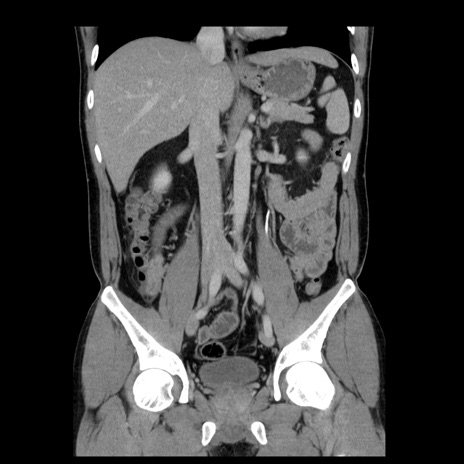

症例4(冠状断像)

【症例】30歳代男性

【主訴】腹痛、嘔吐

【現病歴】昨晩から突然の腹痛あり、その後嘔吐、軟便も出現。腹痛が改善しないため救急搬送となる。2日前にしめ鯖の食事歴あり。

【身体所見】意識清明、苦悶様、BP 135/90mmHg、BT 35.7℃、腹部:平坦、やや硬、心窩部〜臍部に自発痛、圧痛あり、筋性防御+、反跳痛-

【データ】WBC 8100、CRP 0.57